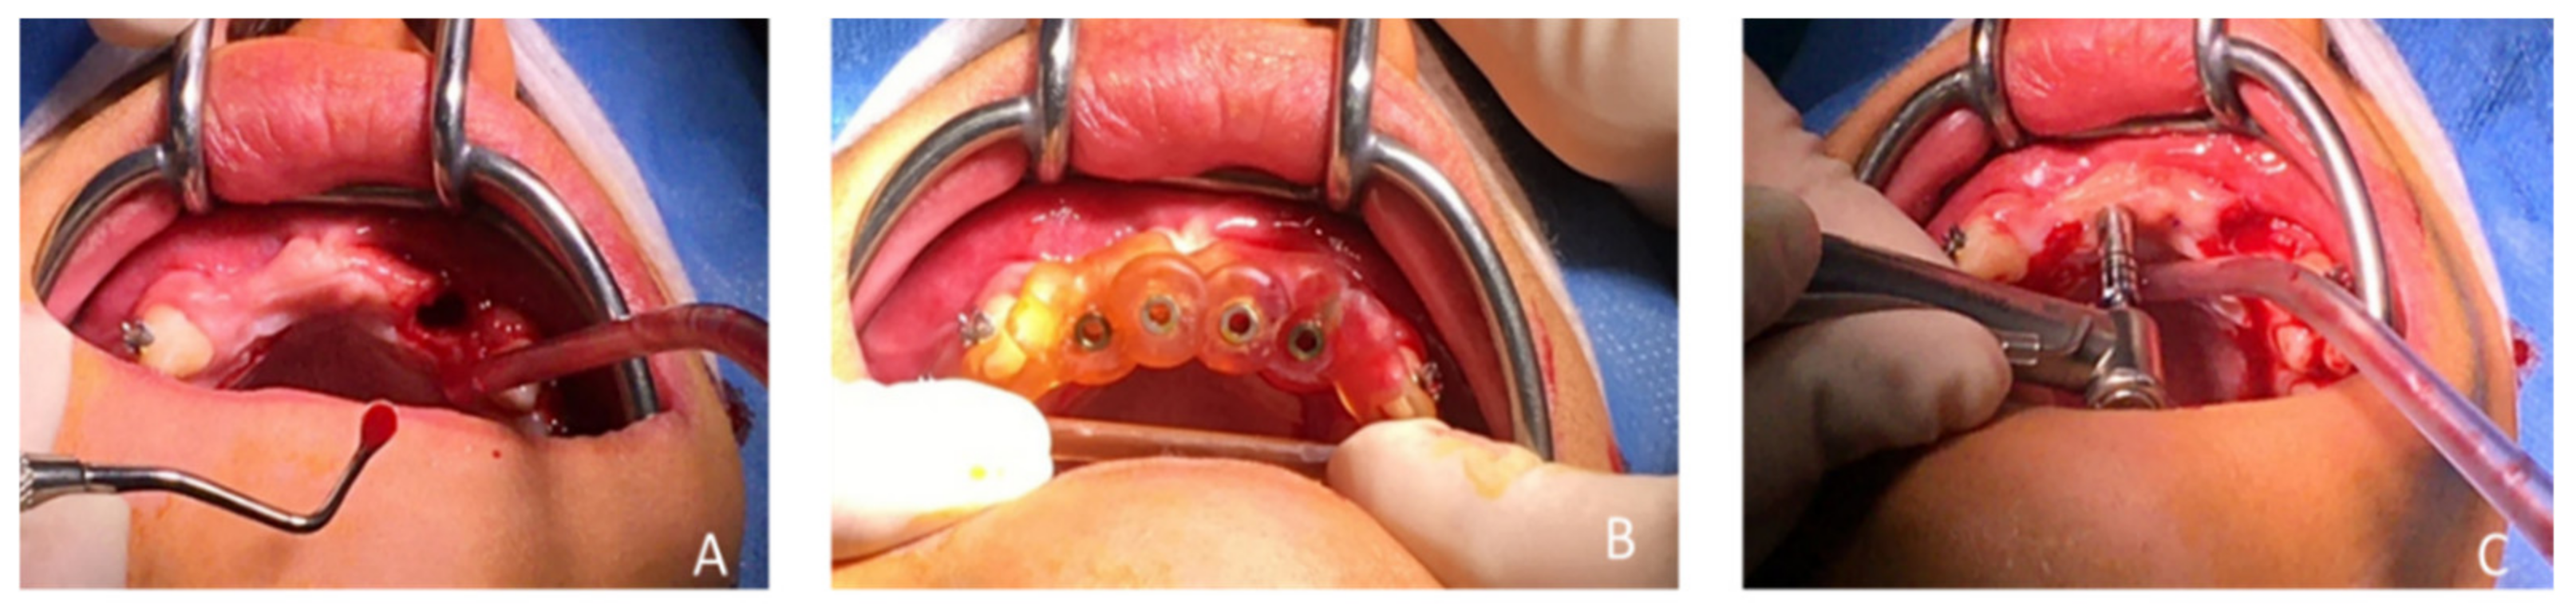

| May 2018 | Buccal and palatal flap of upper right anterior teeth without discharge/curettage of the granulation tissue/endodontic (lesion was of interest to the pulp)/restoration with a composite resin under dam/endodontics treatment with sodium hypochlorite irrigation and obturation at BioRoot™ and calibrated cone | Buccal flap without discharge from upper left anterior teeth/curettage of the granulation tissue/restoration with a composite resin under dam | ||

| Preservation of the bone capital until the implant solution | ||||

| Figure 6 and Figure 7 | ||||